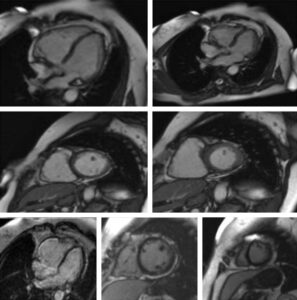

In ambito cardiologico la RM viene richiesta per molteplici ragioni tra le quali il riconoscimento e la quantificazione dell’ischemia miocardica, delle cardiomiopatie sia congenite che acquisite, delle miocarditi e delle patologie del pericardio e rappresenta l’indagine di primo livello nella quantificazione della fibrosi cardiaca e delle cicatrici miocardiche.

La sua elevata definizione consente inoltre un appropriato studio delle sezioni destre del cuore spesso di difficile valutazione con altre metodiche, ecocardiografia compresa. Qualora la tecnica venga applicata al distretto vascolare, generalmente per la definizione di anomalie di decorso o diametro di arterie, si parla di ANGIORM specificandone il distretto (ad es cerebrale, toracico, addominale…).